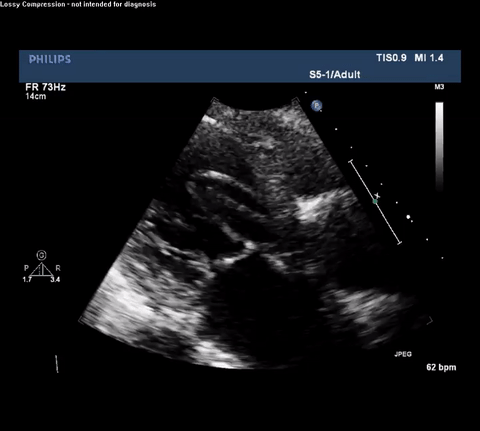

Cardiac point-of-care ultrasound (POCUS) was performed and a representative video was obtained.

TTE Parasternal Long Axis View

Type A acute aortic dissection (TA-AAD). Cardiac POCUS imaging in the

parasternal long axis revealed the intima of the ascending aorta undulating in

and out of the left ventricular outflow tract throughout the cardiac cycle,

consistent with a TA-AAD.